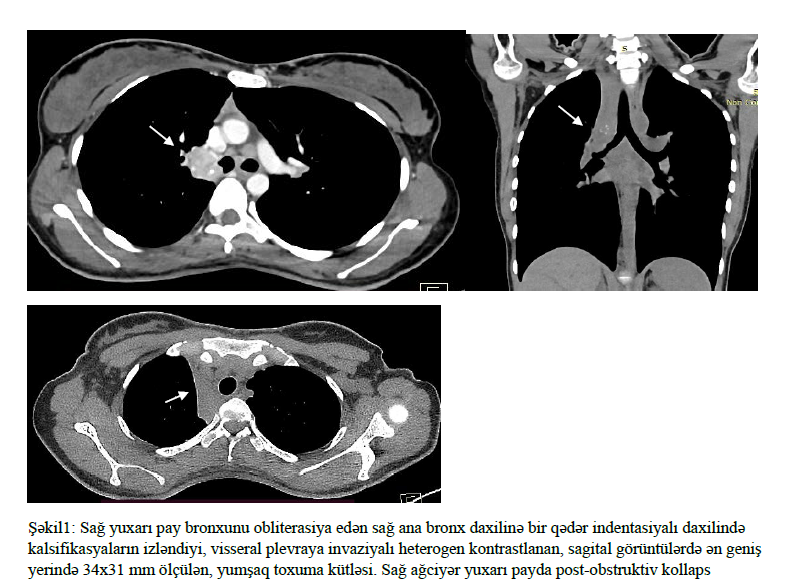

Ağciyər karsinoid şişləri, pulmonar neyroendokrin şişlər olaraq tanınır və ağciyərin nadir rast gəlinən şişlərindən biridir. Bu şişlər, xüsusilə Tipik karsinoid tipi, digər ağciyər xərçəngi tipləri ilə müqayisədə daha yaxşı proqnoza malikdir. Bununla belə, bəzi hallarda xəstələrdə xəstəliyin təkrarlanması və metastaz müşahidə edilə bilər. 24 yaşlı xəstənin sağ ağciyər yuxarı payında post-obstruktiv kollaps və hemoptizi şikayəti olduğu halda, yalnız 2 il sonra Tipik Karsinoid Şiş diaqnozu qoyulmuşdur. Bu fakt, Tipik karsinoid şişlərin yavaş irəliləməsinə baxmayaraq, erkən diaqnostikanın və multidisiplinar yanaşmanın xəstələrin müalicə və proqnozlarına əhəmiyyətli təsir göstərdiyini vurğulamağa imkan verir. Ağciyər karsinoid şişləri bütün neyroendokrin şişlərin 20-30%-ni və ağciyər mənşəli xərçənglərin təxminən 1-2%-ni təşkil edən nadir rast gəlinən şişlərdir. Ağciyər karsinoidlər digər ağciyər xərçəngi alt tipləri ilə müqayisədə daha yaxşı sağqalma göstəricisinə malikdirlər (1,2). Karsinoid ağciyər şişləri daha çox döş qəfəsində ağrı, xırıltı, hemoptizi, post-obstruktiv kollaps və ya post-obstruktiv pnömoni, əlamətləri və simptomları ilə qarşımıza çıxabiler. Təqdim edəcəyimiz klinik halda hemoptizidən 2 il sonra diaqnozu qoyulmuş sağ ağciyərin aşağı dərəcədə differensiya edilmiş (G1) karsinoid şişindən bəhs edilmişdir. Klinik hal 24 yaşlı xəstə 2 ildir davam edən hemoptizi, döş qəfəsində ağrı və döş qəfəsində xışıltı şikayəti ilə klinikamıza müraciət etmişdir. Yanaşı gedən xəstəliyi yoxdur. Fiziki müayinədə ağciyərlər üzərində yayılmış bilateral xırıltılar eşidildi. Saturasiya otaq havasında SpO2 86% ölçüldü. Laborator analizlərində dəyərləri normal aralıqdaydı. Çəkilən PAAG’de sağ üst zonda atelektazi olması səbəbiylə döş qəfəsi KT planlandı. Döş qəfəsi KT’də sternum cismində 30x32 mm ölçüdə santarli litik sklerotik lezyon izlənildi, sağ ağciyər hilusunda sağ yuxarı pay bronxunu obliterasiya edən sağ ana bronx daxilinə bir qədər indentasiyalı daxilində kalsifikasyaların izləndiyi, visseral plevraya invaziyalı heterogen kontrastlanan, sagital görüntülərdə ən geniş yerində 34x31 mm ölçülən, yumşaq toxuma kütləsi, sağ ağciyər yuxarı payda post-obstruktiv kollaps izlənildi (şəkil 1). Mediastinumda, sağ ana bronx qonşuluğunda, karina səviyyəsində orta xəttin solunda, sol ana bronxun anterior qonşuluğunda 14x12 mm ölçülən limfa düyünlər (LAP) izlənildi. Sternum cisminde 3 sm ölçüde sklerotik lezyon (metastaz?), dalaq parenximasında nonspesifik 6 mm ölçüdə hipodens struktur izlənildi. (şəkil 2). Xəstəyə bronxoskopiya planlandı. Bronkoskopiya zamanı sağ üst lob mənfəzini tama yaxın bağlayan ve sağ ana endobronşiyal lümenə uzanan lezyon görüldü, forceps biyopsiya alındı. Patologiya nəticəsi Karsinoid tümör, NOS şəklində raporlandı. Xəstəyə karsinoid tümör diaqnozu ilə lobektomiya, limfadenektomiya edildi (şəkil 3). Rezeksiyon materialın patoloji nəticəsində tipik karsinoid tümör və limfalarda non nekrotizan qranülomatoz iltihab görüldü. Non nekrotizan qranülomatoz iltihab paraneoplastik sendrom olan sarkoid benzer reaksiyona bağlı olabiləcəyi düşünüldü. Xəstəyə əməliyyatdan 2 ay sonra kontrol döş qəfəsi KT planlandı.